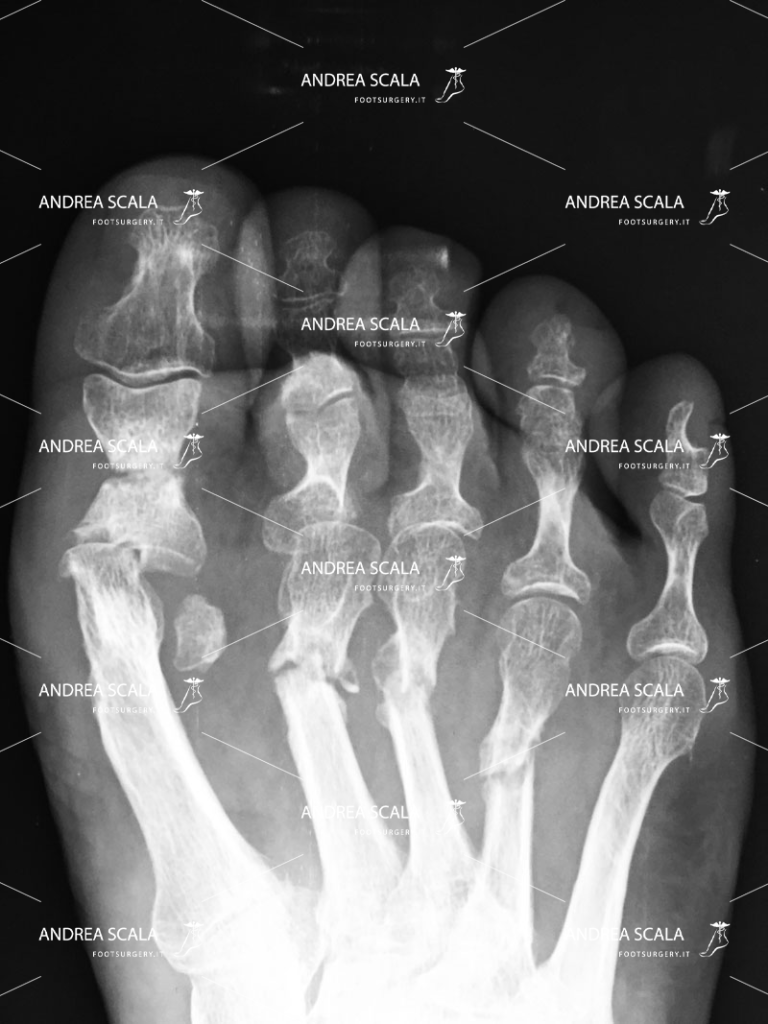

Con il termine “alluce valgo” ci si riferisce a una patologia che non colpisce propriamente solo l’alluce, ma tutta la parte anteriore del piede. Molto semplicemente, si tratta di una deviazione dell’alluce verso l’interno, ovvero verso le altre dita, che causa un particolare rigonfiamento laterale in corrispondenza della testa del primo metatarso.

Questa tencnica prevede l’uso di un frullino che viene messo sotto la pelle della paziente (percutanea). Il chirurgo quarda la Rxgrafia, ma non osserva con gli occhi ciò che sta facendo sotto la pelle (percutanea). Il frullino ad alta velocità taglia l’osso e alcune volte anche tendini, vasi e nervi. Al termine dell’intervento l’osso tagliato viene lasciato libero di guarire senza alcun sostegno e senza alcuna guida. Osserviamo in ambulatorio casi molto gravi in cui l’osso è guarito storto o non si è più riattaccato.

L’operazione dell’alluce eseguita con tecnica mininvasiva (con una minima incisione).

Il dott. Andrea Scala ha messo a punto una tecnica, pubblicata in U.S.A. nel 2013 che supera i problemi che la tecnica percutanea comporta.

Grazie a questa tecnica è possibile sezionare l’osso deformato per riposizionarlo e riallinearlo con le altre dita del piede, il tutto effettuando solo un’incisione di pochi millimetri sulla cute. La minima incisione taglia l’osso con precisione ed evita di tagliare anche tendini, vasi e nervi. Al termine dell’intervento un piccolo chiodo di 1 millimetro aiuta l’osso tagliato a guarire nella posizione corretta e assicura che l’alluce operato non tornerà mai più.